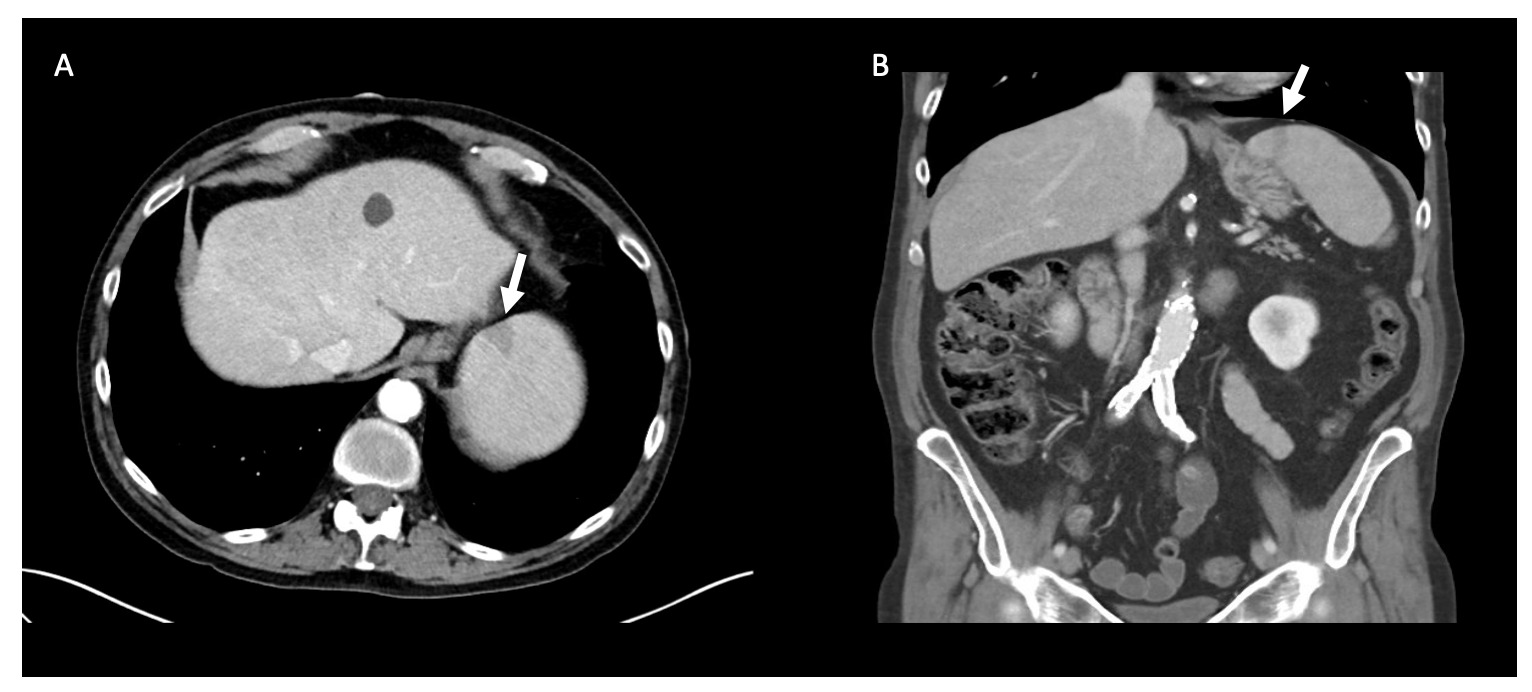

Laboratory analysis was notable for an AST of 95 IU/L and ALT of 74 IU/L, a white blood cell count of 2.5x 109/L (normal, 4.2-10.0 x 109), hemoglobin of 10.3 g/dL, and a platelet count of 23,000 plt/mm3. His respiratory pathogen panel and urine legionella were negative. Peripheral blood smear was positive for intraerythrocytic ring form parasites, with an initial parasitemia level of 0.81%. CT abdomen pelvis with IV contrast demonstrated multiple splenic infarcts and trace perisplenic fluid (Figure 4). These infarcts were attributed to babesiosis infection, though no echocardiogram was performed to formally confirm absence of infectious endocarditis or cardiac emboli. He was started on atovaquone and azithromycin to treat Babesia microti and was empirically treated with doxycycline for other tick-borne diseases including anaplasmosis, ehrlichiosis, and Lyme Disease. He was also started on piperacillin-tazobactam to cover for other occult infection sources in the setting of severe sepsis. Anticoagulation was not recommended for his multiple splenic infarcts due to thrombocytopenia. Due to an abrupt change in mental status, a CT brain without IV contrast was performed and revealed a 6 mm right-sided subdural hematoma. A repeat CT brain without IV contrast 6 hours later confirmed the stability of this hematoma, and he was transfused one dose of platelets in the setting of an intracranial hemorrhage.